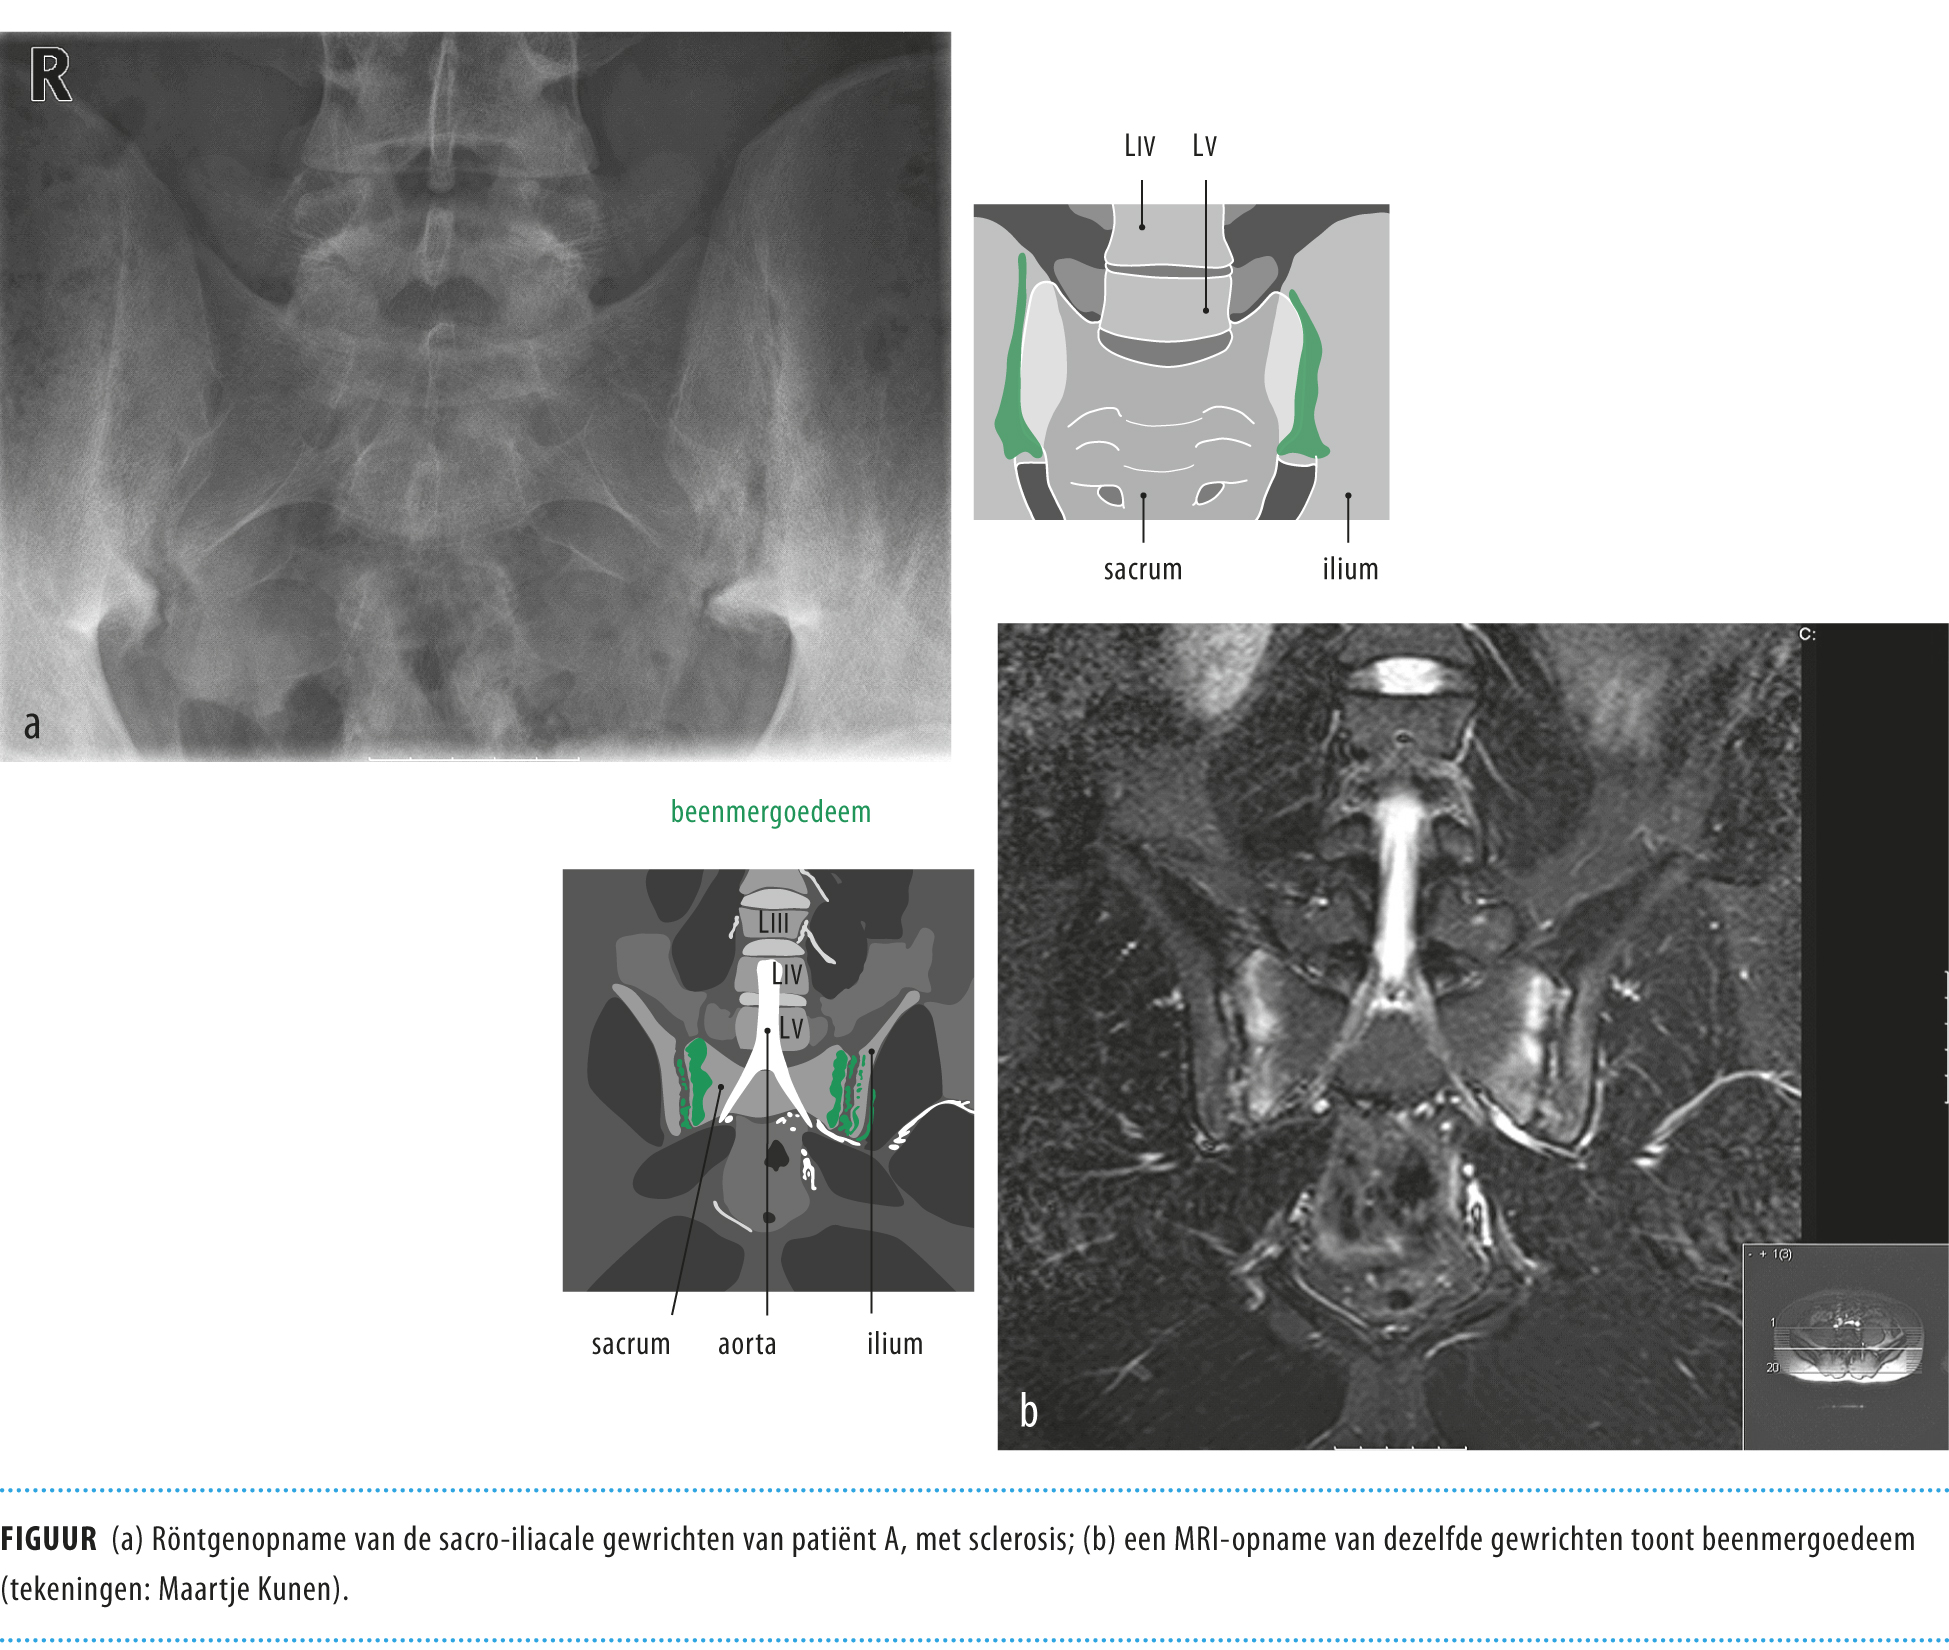

(PDF) Spondyloartritis en ankyloserende spondylitis (AS)...• ankyloserende spondylitis (de